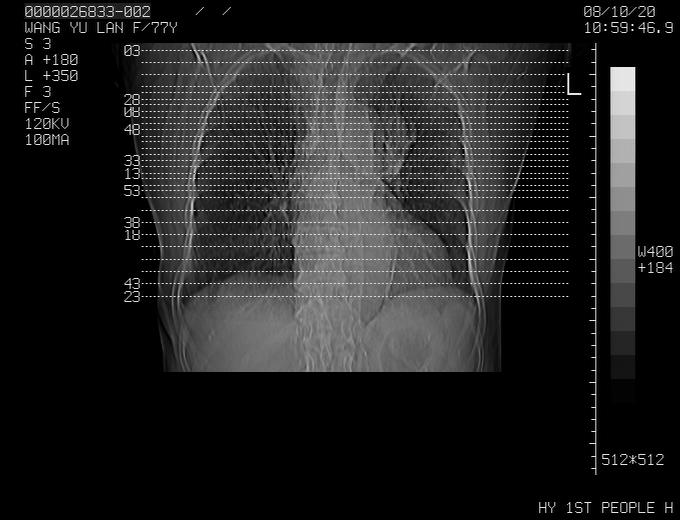

支持楼主,    但是做个矢冠状面成像就完美了